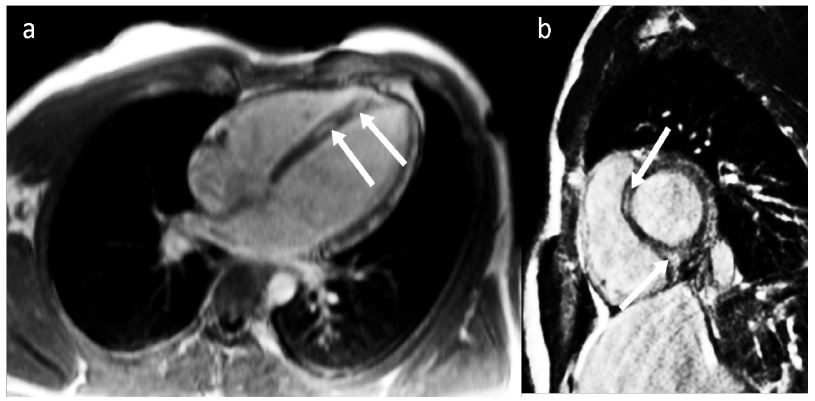

Echocardiography did not show any particularity. Cardiac MRI showed late enhancement at the septo-apical level (Figure 2). The diagnosis of acute myocarditis was retained.

Figure 2: Four-cavity (a) and short-axis (b) cardiac MRI showing late gadolinium enhancement in septal wall, suggestive of myocarditis.